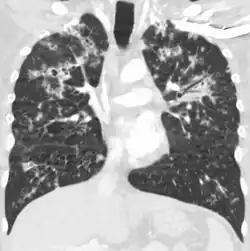

Tuberculosis of the lungs

Testing for miliary tuberculosis is conducted in a similar manner as for other forms of tuberculosis, although a number of tests must be conducted on a patient to confirm diagnosis.[3] Tests include chest x-ray, sputum culture, bronchoscopy, open lung biopsy, head CT/MRI, blood cultures, fundoscopy, and electrocardiography.[9] The tuberculosis (TB) blood test, also called an Interferon Gamma Release Assay or IGRA, is a way to diagnose latent TB. A variety of neurological complications have been noted in miliary tuberculosis patients—tuberculous meningitis and cerebral tuberculomas being the most frequent. However, a majority of patients improve following antituberculous treatment. Rarely lymphangitic spread of lung cancer could mimic miliary pattern of tuberculosis on regular chest X-ray. [14]

A case of miliary tuberculosis in an 82-year-old woman: